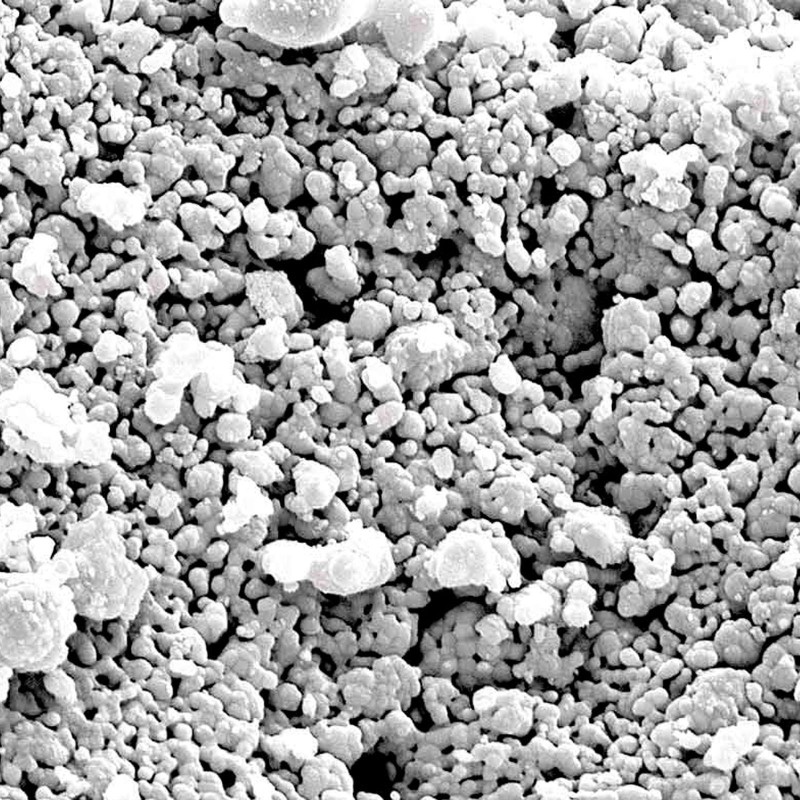

SUPERFICIE MUY RUGOSA E HIDRÓFILA 100% SINTÉTICO Y REABSORBIBLE PROPIEDADES OSTEOCONDUCTIVAS IDEALES

Maxresorb ® es un material sustituto óseo innovador, seguro, confiable y totalmente sintético que se caracteriza por una reabsorción controlada y excelentes características de manipulación. maxresorb ® está compuesto por un 60% de hidroxiapatita (HA) de lenta absorción y un 40% de beta-fosfato tricálcico (β-TCP) de rápida absorción 1,2 . El exclusivo proceso de producción basado en síntesis garantiza una distribución completamente homogénea de ambas fases minerales. La composición especial de maxresorb ® promueve la rápida formación de nuevo hueso vital y asegura una reabsorción controlada sin pérdida de volumen del sitio aumentado.

Superficie muy rugosa e hidrófila 100 % sintético y reabsorbible, propiedades osteoconductivas ideales.

Maxresorb ® es un material sustituto óseo innovador, seguro, confiable y totalmente sintético que se caracteriza por una reabsorción controlada y excelentes características de manipulación. maxresorb ® está compuesto por un 60% de hidroxiapatita (HA) de lenta absorción y un 40% de beta-fosfato tricálcico (β-TCP) de rápida absorción 1,2 . El exclusivo proceso de producción basado en síntesis garantiza una distribución completamente homogénea de ambas fases minerales. La composición especial de maxresorb ® promueve la rápida formación de nuevo hueso vital y asegura una reabsorción controlada sin pérdida de volumen del sitio aumentado.

Porosidad interconectada ultra alta

La osteoconductividad de maxresorb ® se basa en una red de poros interconectados, una porosidad total muy alta de aprox. 80% así como su superficie muy rugosa 3, 4, 5 . La superficie nanoestructurada facilita la adsorción de sangre, proteínas y células madre y promueve la diferenciación celular y la integración ósea. maxresorb ® es, por lo tanto, un andamio ideal para la migración de células formadoras de hueso y la unión de moléculas de señalización, que pueden acelerar la integración y regeneración del tejido 6, 7 .